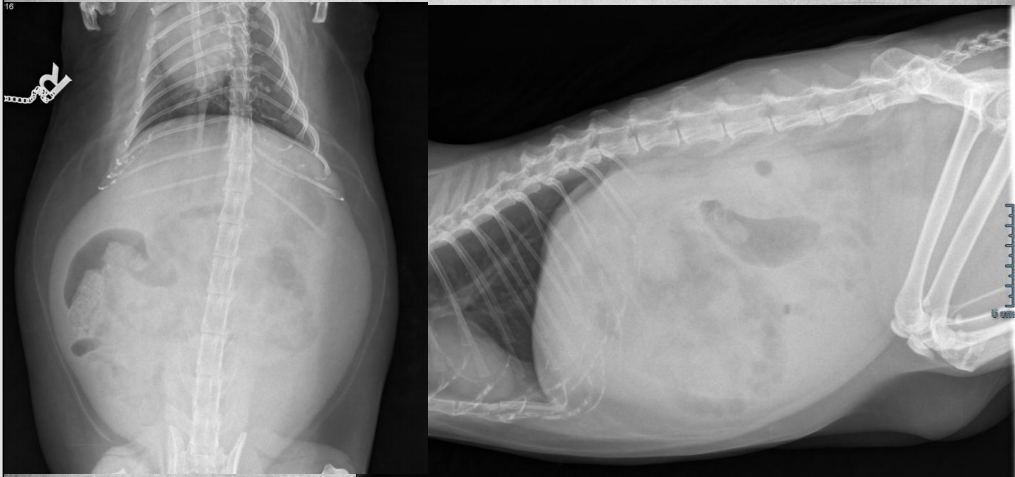

●10 yo female sterilized rottweiler

●Vomiting after every meal for 2 days

● Soft tissue opacity in the area of stomach

● Metal staple in colon

● Metal implant in one knee (from

previous surgery)

● Soft foreign body in stomach – grass,

fabric, wrapping paper

major organs in abdo cavity are hazy and poorly viewed, and lumen of stomach not viewable due to fabric foreign body in stomach.

cecum visible on VD, gas filled bubbles.